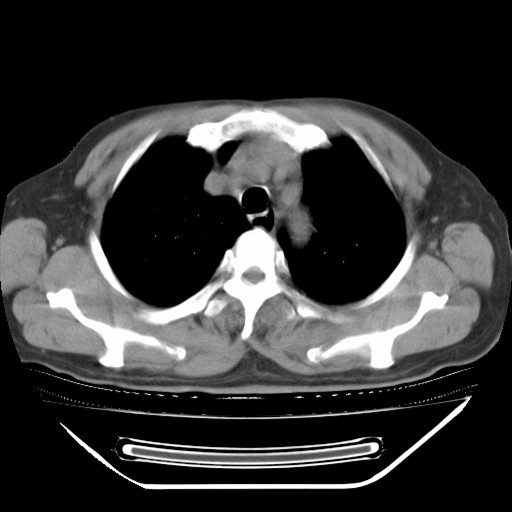

以下是引用hhcckk在2009-5-29 10:34:00的发言:[br]左下肺片絮状边缘模糊影,考虑感染,建议治疗后复查[br]